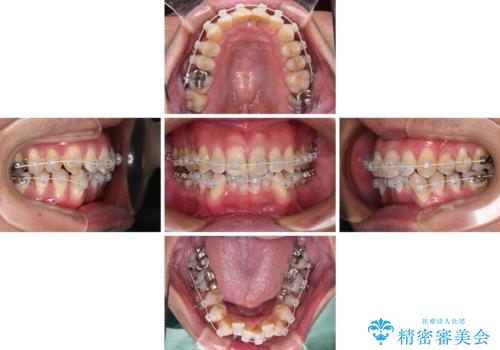

下顎にワイヤー装置を装着し、暫くしたところでやはりインビザラインにて矯正治療をしたいとのことで、インビザラインに切り替えました。

短い期間でしたがワイヤー装置を使用したことでデコボコが解消されたため、インビザラインの比較的短い期間で矯正治療を行うことができました。

- インビザライン・審美装置